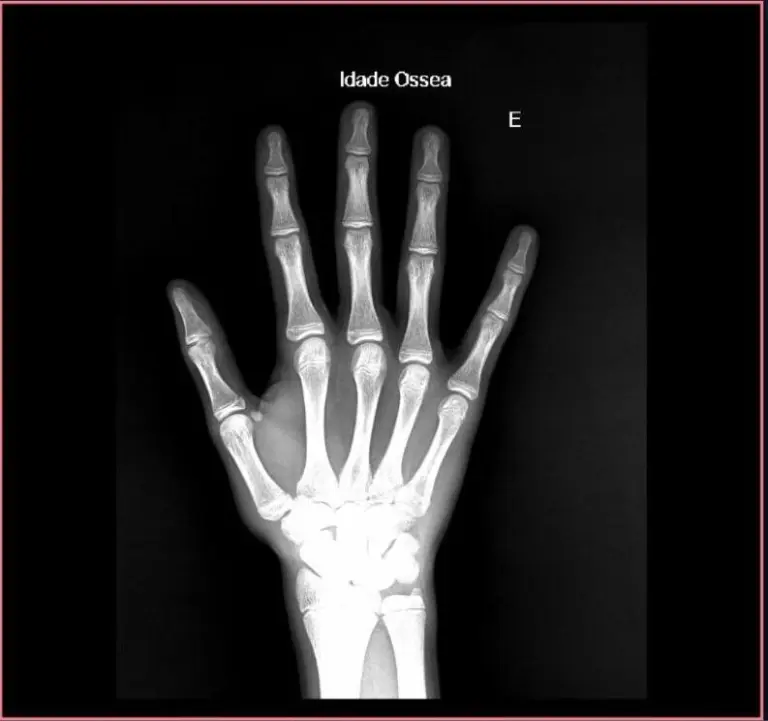

Cálculo de edad ósea con IA en rayos X de manos y muñecas

Herramientas con este enfoque son capaces de estimar la madurez ósea de un individuo basándose en las dimensiones presentadas en la imagen de rayos X de manos y muñecas.

El análisis de edad ósea es especialmente relevante en áreas relacionadas con la pediatría. En este caso, el algoritmo de cálculo tiene mayor relevancia como base de apoyo para el diagnóstico del médico responsable.